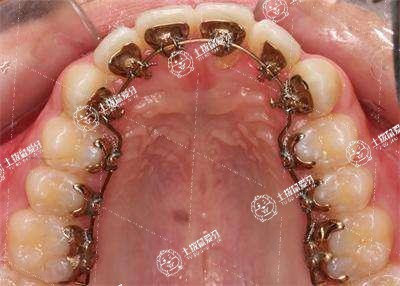

矯正之前可以先去相關(guān)的口腔科給醫(yī)生面診,治療價(jià)格跟每個(gè)人的治療方案有關(guān)。傳統(tǒng)的鋼絲矯正地包天價(jià)格大概要6000元左右,無(wú)托槽隱形矯正基本上都要20000元左右半口不等,要拔牙,而且鋼絲矯正和無(wú)托槽隱形矯正要耗時(shí)達(dá)兩年之久,兩年過(guò)后還要帶半年的保質(zhì)器以防復(fù)發(fā),而且往返醫(yī)院數(shù)十次更讓很多愛(ài)美人士消受不起。具體成人牙齒正畸多少錢(qián),可咨詢當(dāng)?shù)蒯t(yī)療機(jī)構(gòu)。

2. 如果是簡(jiǎn)單的矯正,比如牙齒有輕微的擁擠或者錯(cuò)位,費(fèi)用會(huì)比較低,大概在2000-5000元左右。

3. 如果需要進(jìn)行復(fù)雜的矯正,比如需要拔牙或者進(jìn)行頜骨手術(shù)等,費(fèi)用就會(huì)相應(yīng)的增加,大概在10,000-30,000元之間。

4. 另外,如果需要單獨(dú)安裝隱形矯正器,費(fèi)用也會(huì)相應(yīng)增加,一般在15,000-25,000元左右。